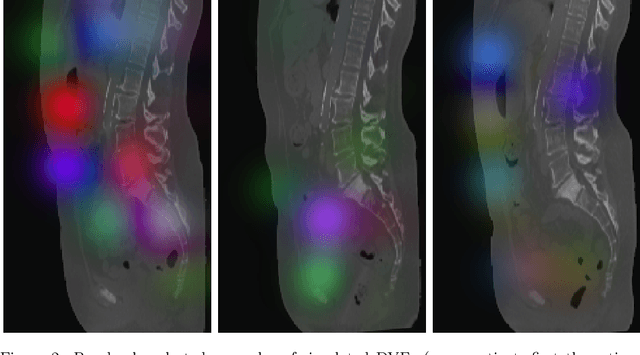

Abstract:High-grade serous ovarian carcinoma (HGSOC) is characterised by significant spatial and temporal heterogeneity, typically manifesting at an advanced metastatic stage. A major challenge in treating advanced HGSOC is effectively monitoring localised change in tumour burden across multiple sites during neoadjuvant chemotherapy (NACT) and predicting long-term pathological response and overall patient survival. In this work, we propose a self-supervised deformable image registration algorithm that utilises a general-purpose image encoder for image feature extraction to co-register contrast-enhanced computerised tomography scan images acquired before and after neoadjuvant chemotherapy. This approach addresses challenges posed by highly complex tumour deformations and longitudinal lesion matching during treatment. Localised tumour changes are calculated using the Jacobian determinant maps of the registration deformation at multiple disease sites and their macroscopic areas, including hypo-dense (i.e., cystic/necrotic), hyper-dense (i.e., calcified), and intermediate density (i.e., soft tissue) portions. A series of experiments is conducted to understand the role of a general-purpose image encoder and its application in quantifying change in tumour burden during neoadjuvant chemotherapy in HGSOC. This work is the first to demonstrate the feasibility of a self-supervised image registration approach in quantifying NACT-induced localised tumour changes across the whole disease burden of patients with complex multi-site HGSOC, which could be used as a potential marker for ovarian cancer patient's long-term pathological response and survival.